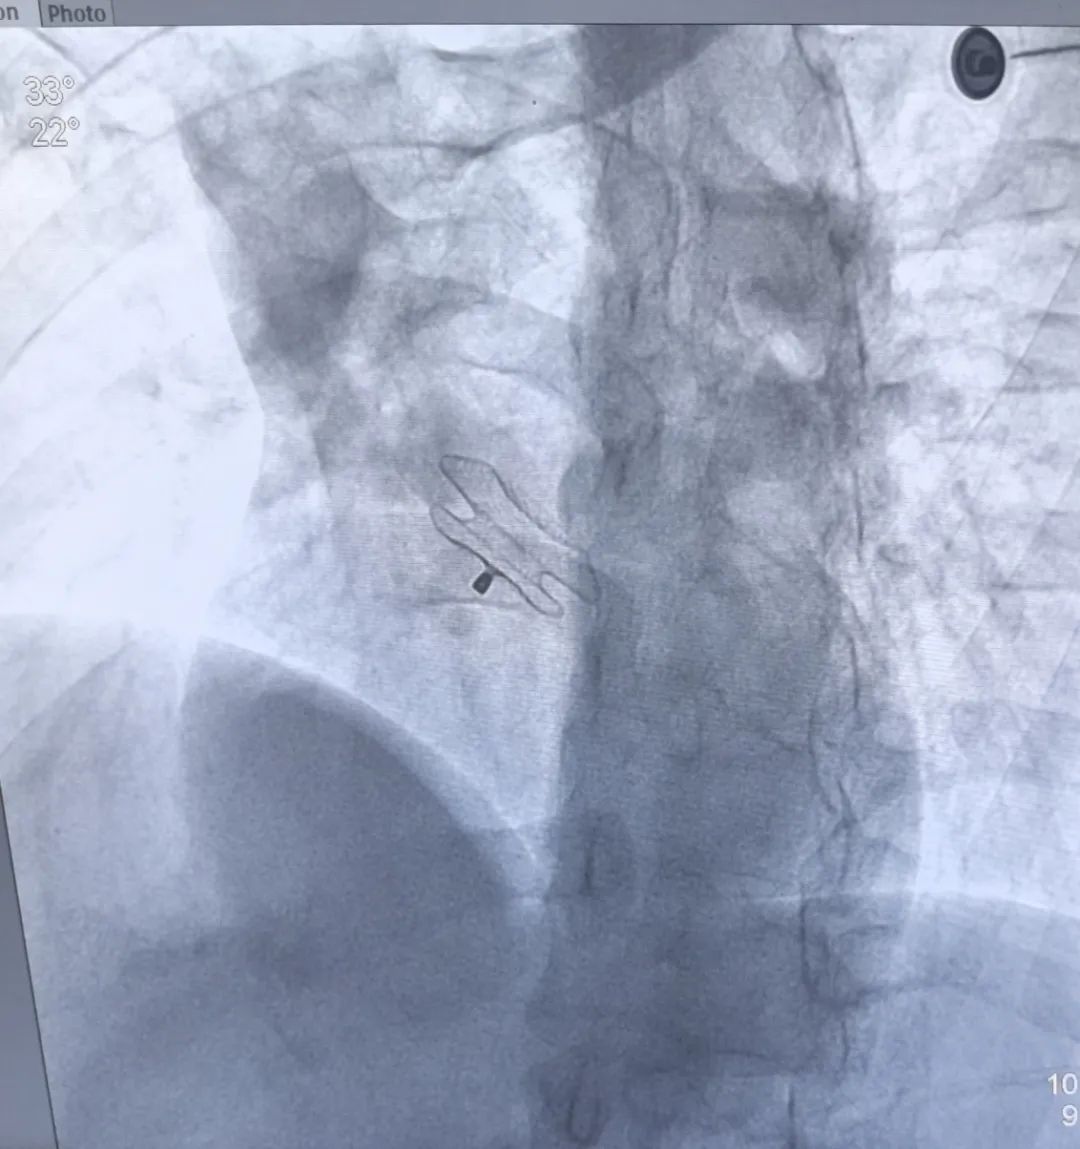

植入材料封堵伞。

在新疆心内科领域权威医师许力舒主任的指导及乌苏市人民医院导管室、心超室的紧密协作下,成功为患者心脏房间隔缺损部位进行了经皮介入封堵治疗。术后彩超见封堵伞位置良好,未见残余过隔血流。

房间隔缺损的治疗:通过介入手术可以将缺损部位进行封堵。①医生在患者大腿根部股静脉穿刺,将导管送至右心室、右心房、左心房进行测压,再通过一根导管将封堵器沿血管输送通过房间隔缺损处至左心房。②封堵器的双面伞状结构紧贴房间隔缺损两侧,将缺口封堵住。治疗过程仅需30分钟左右,安全有效、创口微小,康复后可以与正常人一样生活与学习,重获”心”生。